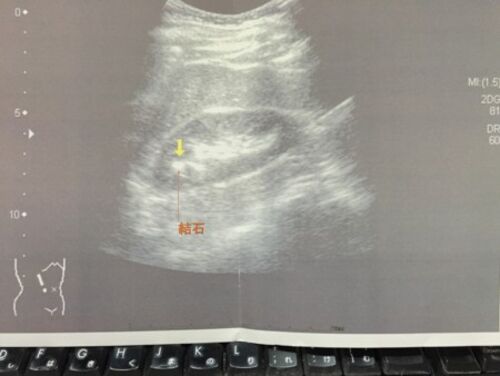

腎結石とともに生きていく

なんだか左の背中脇腹近くが鈍く痛いような気がする。 いや、これは持病の腰痛のはずだ。しかし、それにしては、位置が骨からかなり離れている気がするし、違和感は片方だけだ。 もしかすると。 先日、人間ドックに行ってきた。 去年は、脳のMRIの結果で、閉…